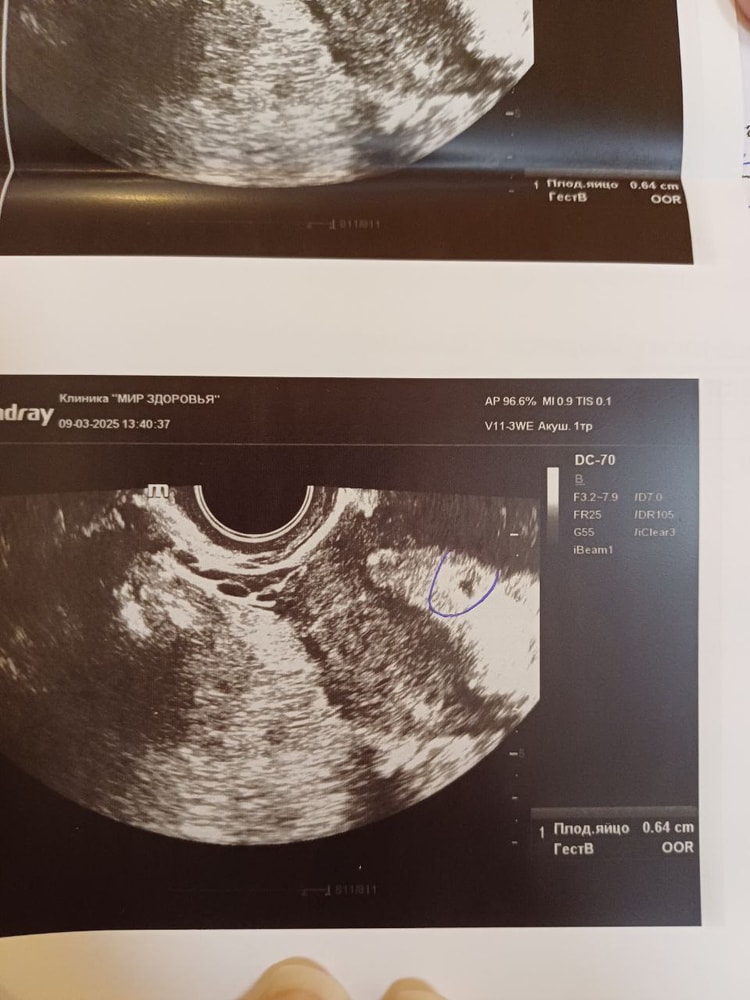

По узи было плодное яйцо 6.4 мм деформированное как клякса без желточного мешка. Мне сказали тут лучше не ждать ничего хорошего и рекомендовали сразу прервать таблетками. Я прервала и до сих пор думаю жалею об этом. Ведь по сути это же был срок 4-5 недель, если считать от овуляции. На таком сроке возможно же такое плодное яйцо? Фото прикрепляю.

Просто сейчас узнала о беременности и боюсь уже раньше 7-8 нед идти на узи, постоянно думаю о той беременности и что поспешила на мед аборт..ведь если я сейчас пойду через неделю на узи, смогу сравнить примерно плодные яйца тогда и сейчас. Я просто делала первое узи тогда 9 марта, а о беременности узнала 1 марта (были слабые полоски мамачек), теперь думаю рано пошла и мед аборт был ошибкой возможно